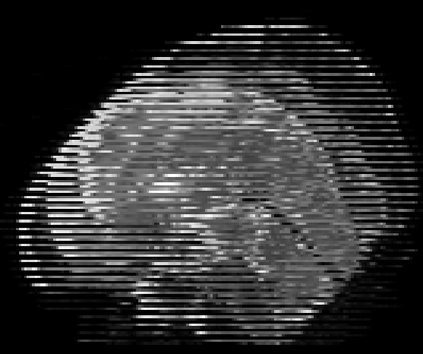

Real-world settings often do not allow acquisition of high-resolution volumetric images for accurate morphological assessment and diagnostic. In clinical practice it is frequently common to acquire only sparse data (e.g. individual slices) for initial diagnostic decision making. Thereby, physicians rely on their prior knowledge (or mental maps) of the human anatomy to extrapolate the underlying 3D information. Accurate mental maps require years of anatomy training, which in the first instance relies on normative learning, i.e. excluding pathology. In this paper, we leverage Bayesian Deep Learning and environment mapping to generate full volumetric anatomy representations from none to a small, sparse set of slices. We evaluate proof of concept implementations based on Generative Query Networks (GQN) and Conditional BRUNO using abdominal CT and brain MRI as well as in a clinical application involving sparse, motion-corrupted MR acquisition for fetal imaging. Our approach allows to reconstruct 3D volumes from 1 to 4 tomographic slices, with a SSIM of 0.7+ and cross-correlation of 0.8+ compared to the 3D ground truth.